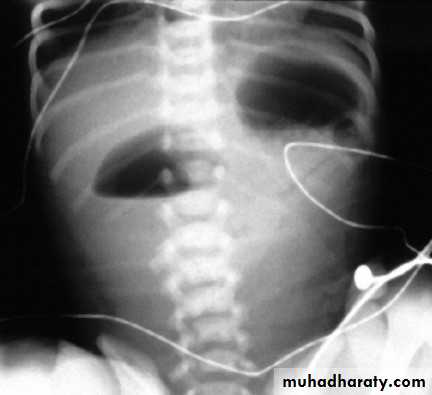

X-ray may show a 'double-bubble' and no gas within the bowel

48